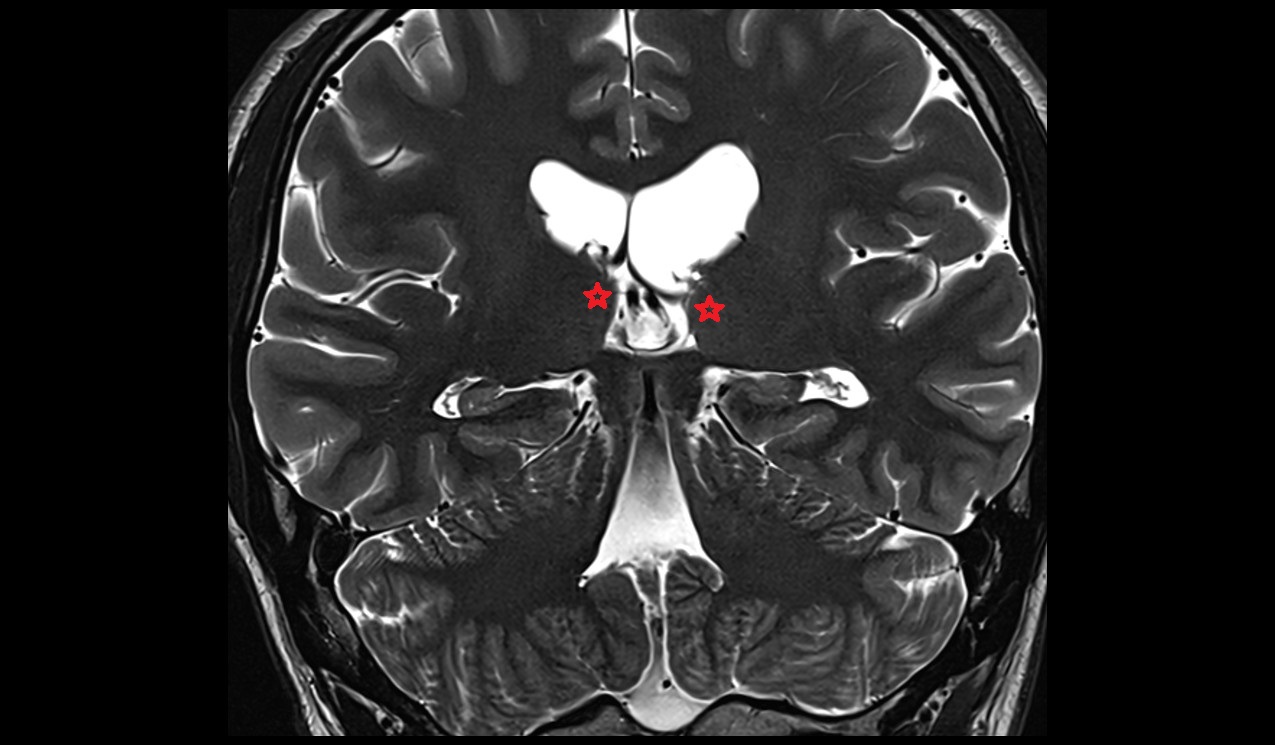

- Hippocampus